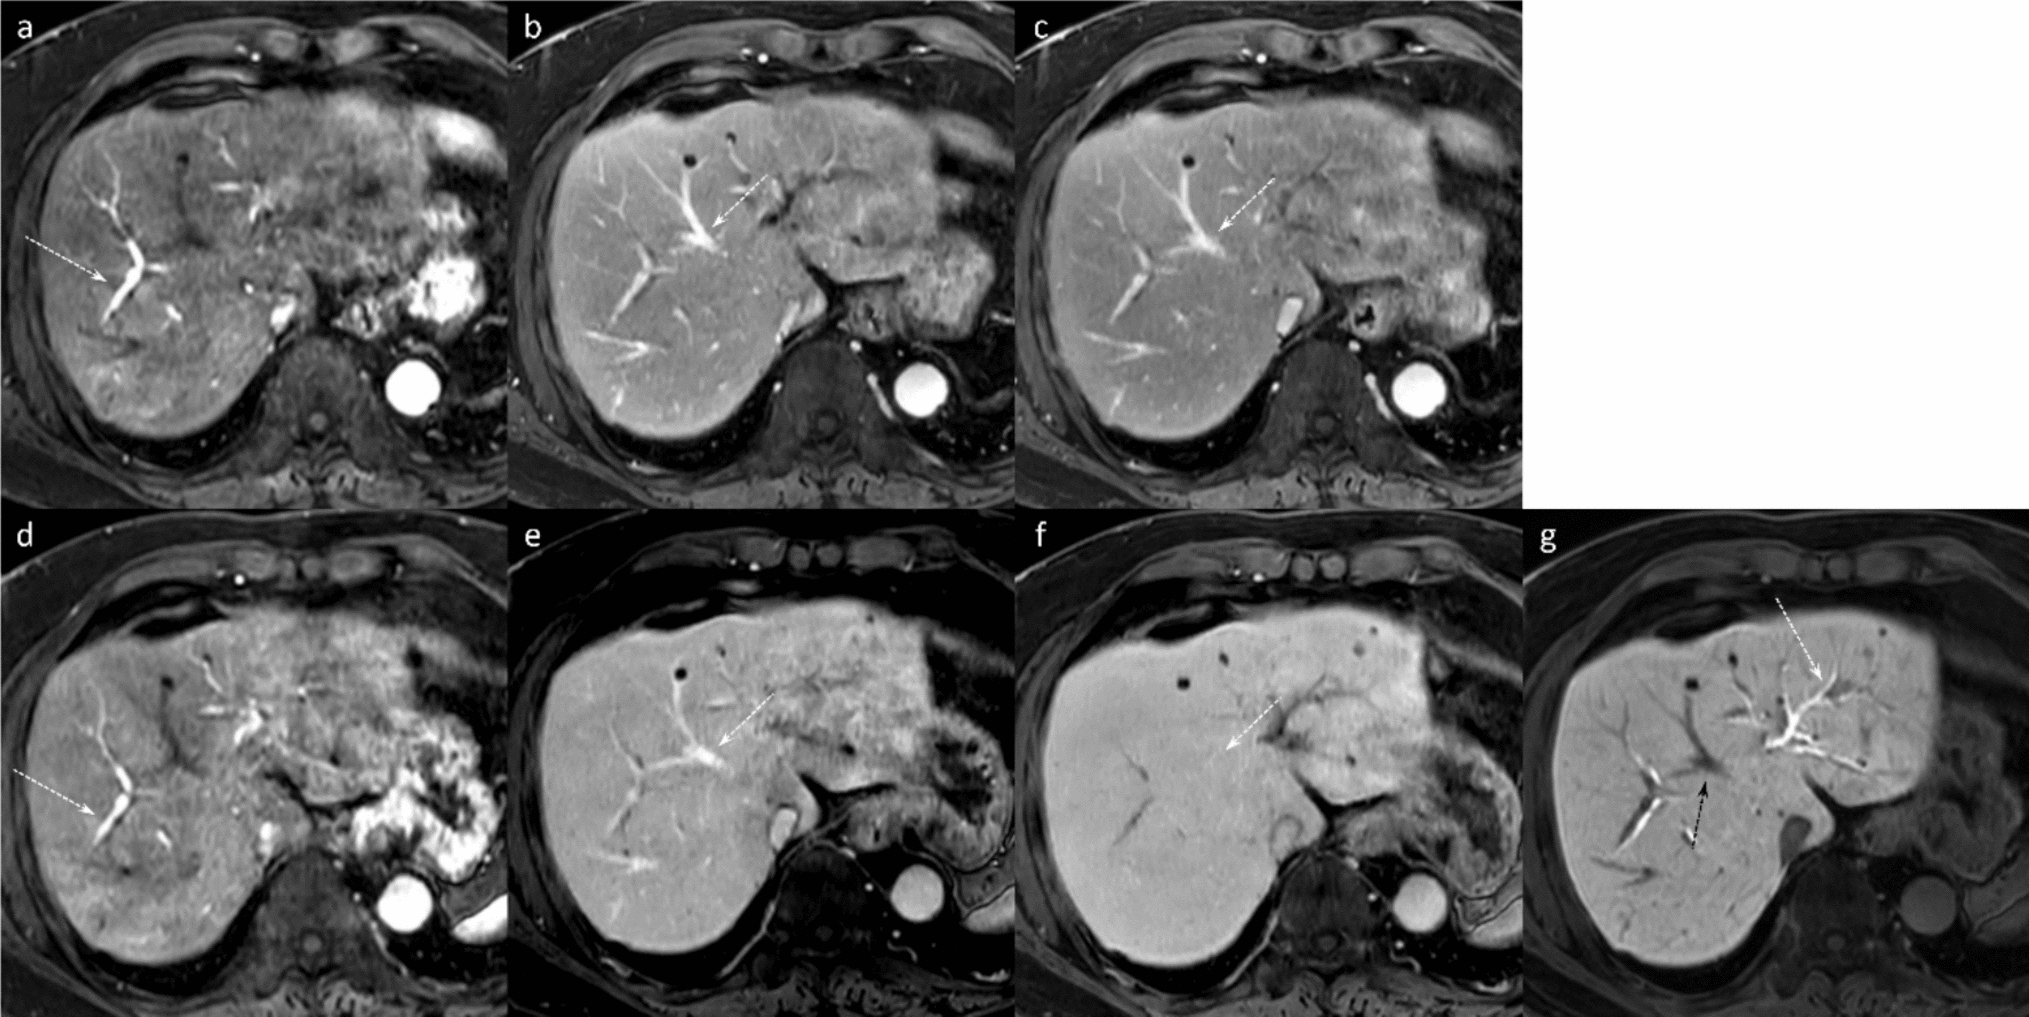

Gadoxetic acid-enhanced MRI in hepatocellular carcinoma: a comprehensive review of diagnostic, surveillance, and treatment response prediction and assessment

Gadoxetic acid-enhanced magnetic resonance imaging (MRI) has become a pivotal imaging modality in hepatocellular carcinoma...